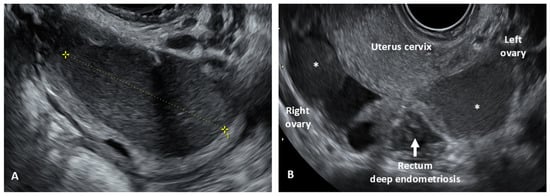

- Deep infiltrating endometriosis (DIE), defined as a lesion infiltrating the peritoneum and involving the retroperitoneal space or the walls of pelvic organs, larger than 5 mm.

- Goncalves, M.O.; Neto, J.S.; Andres, M.P.; Siufi, D.; de Mattos, L.A.; Abrao, M.S. Systematic evaluation of endometriosis by transvaginal ultrasound can accurately replace diagnostic laparoscopy, mainly for deep and ovarian endometriosis. Hum. Reprod. 2021, 36, 1492–1500. [Google Scholar] [CrossRef] [PubMed]

- Condous, G.; Gerges, B.; Thomassin-Naggara, I.; Becker, C.; Tomassetti, C.; Krentel, H.; van Herendael, B.J.; Malzoni, M.; Abrao, M.S.; Saridogan, E.; et al. Non-invasive imaging techniques for diagnosis of pelvic deep endometriosis and endometriosis classification systems: An International Consensus Statement. Ultrasound Obstet. Gynecol. 2024, 64, 129–144. [Google Scholar] [CrossRef]

- Guerriero, S.; Condous, G.; van den Bosch, T.; Valentin, L.; Leone, F.P.; Van Schoubroeck, D.; Exacoustos, C.; Installé, A.J.; Martins, W.P.; Abrao, M.S.; et al. Systematic approach to sonographic evaluation of the pelvis in women with suspected endometriosis, including terms, definitions and measurements: A consensus opinion from the International Deep Endo-metriosis Analysis (IDEA) group. Ultrasound Obstet. Gynecol. 2016, 48, 318–332. [Google Scholar] [CrossRef]

- Martire, F.G.; Russo, C.; Selntigia, A.; Nocita, E.; Soreca, G.; Lazzeri, L.; Zupi, E.; Exacoustos, C. Early noninvasive diagnosis of endometriosis: Dysmenorrhea and specific ultrasound findings are important indicators in young women. Fertil. Steril. 2022, 119, 455–464. [Google Scholar] [CrossRef]